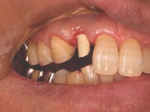

インセラム(オールセラミック)症例①

治療前治療前インセラム(オールセラミック)冠による修復。 主訴は前歯が汚い 金属を使わないオールセラミックでの治療を勧めた。 術前 治療後治療後術後